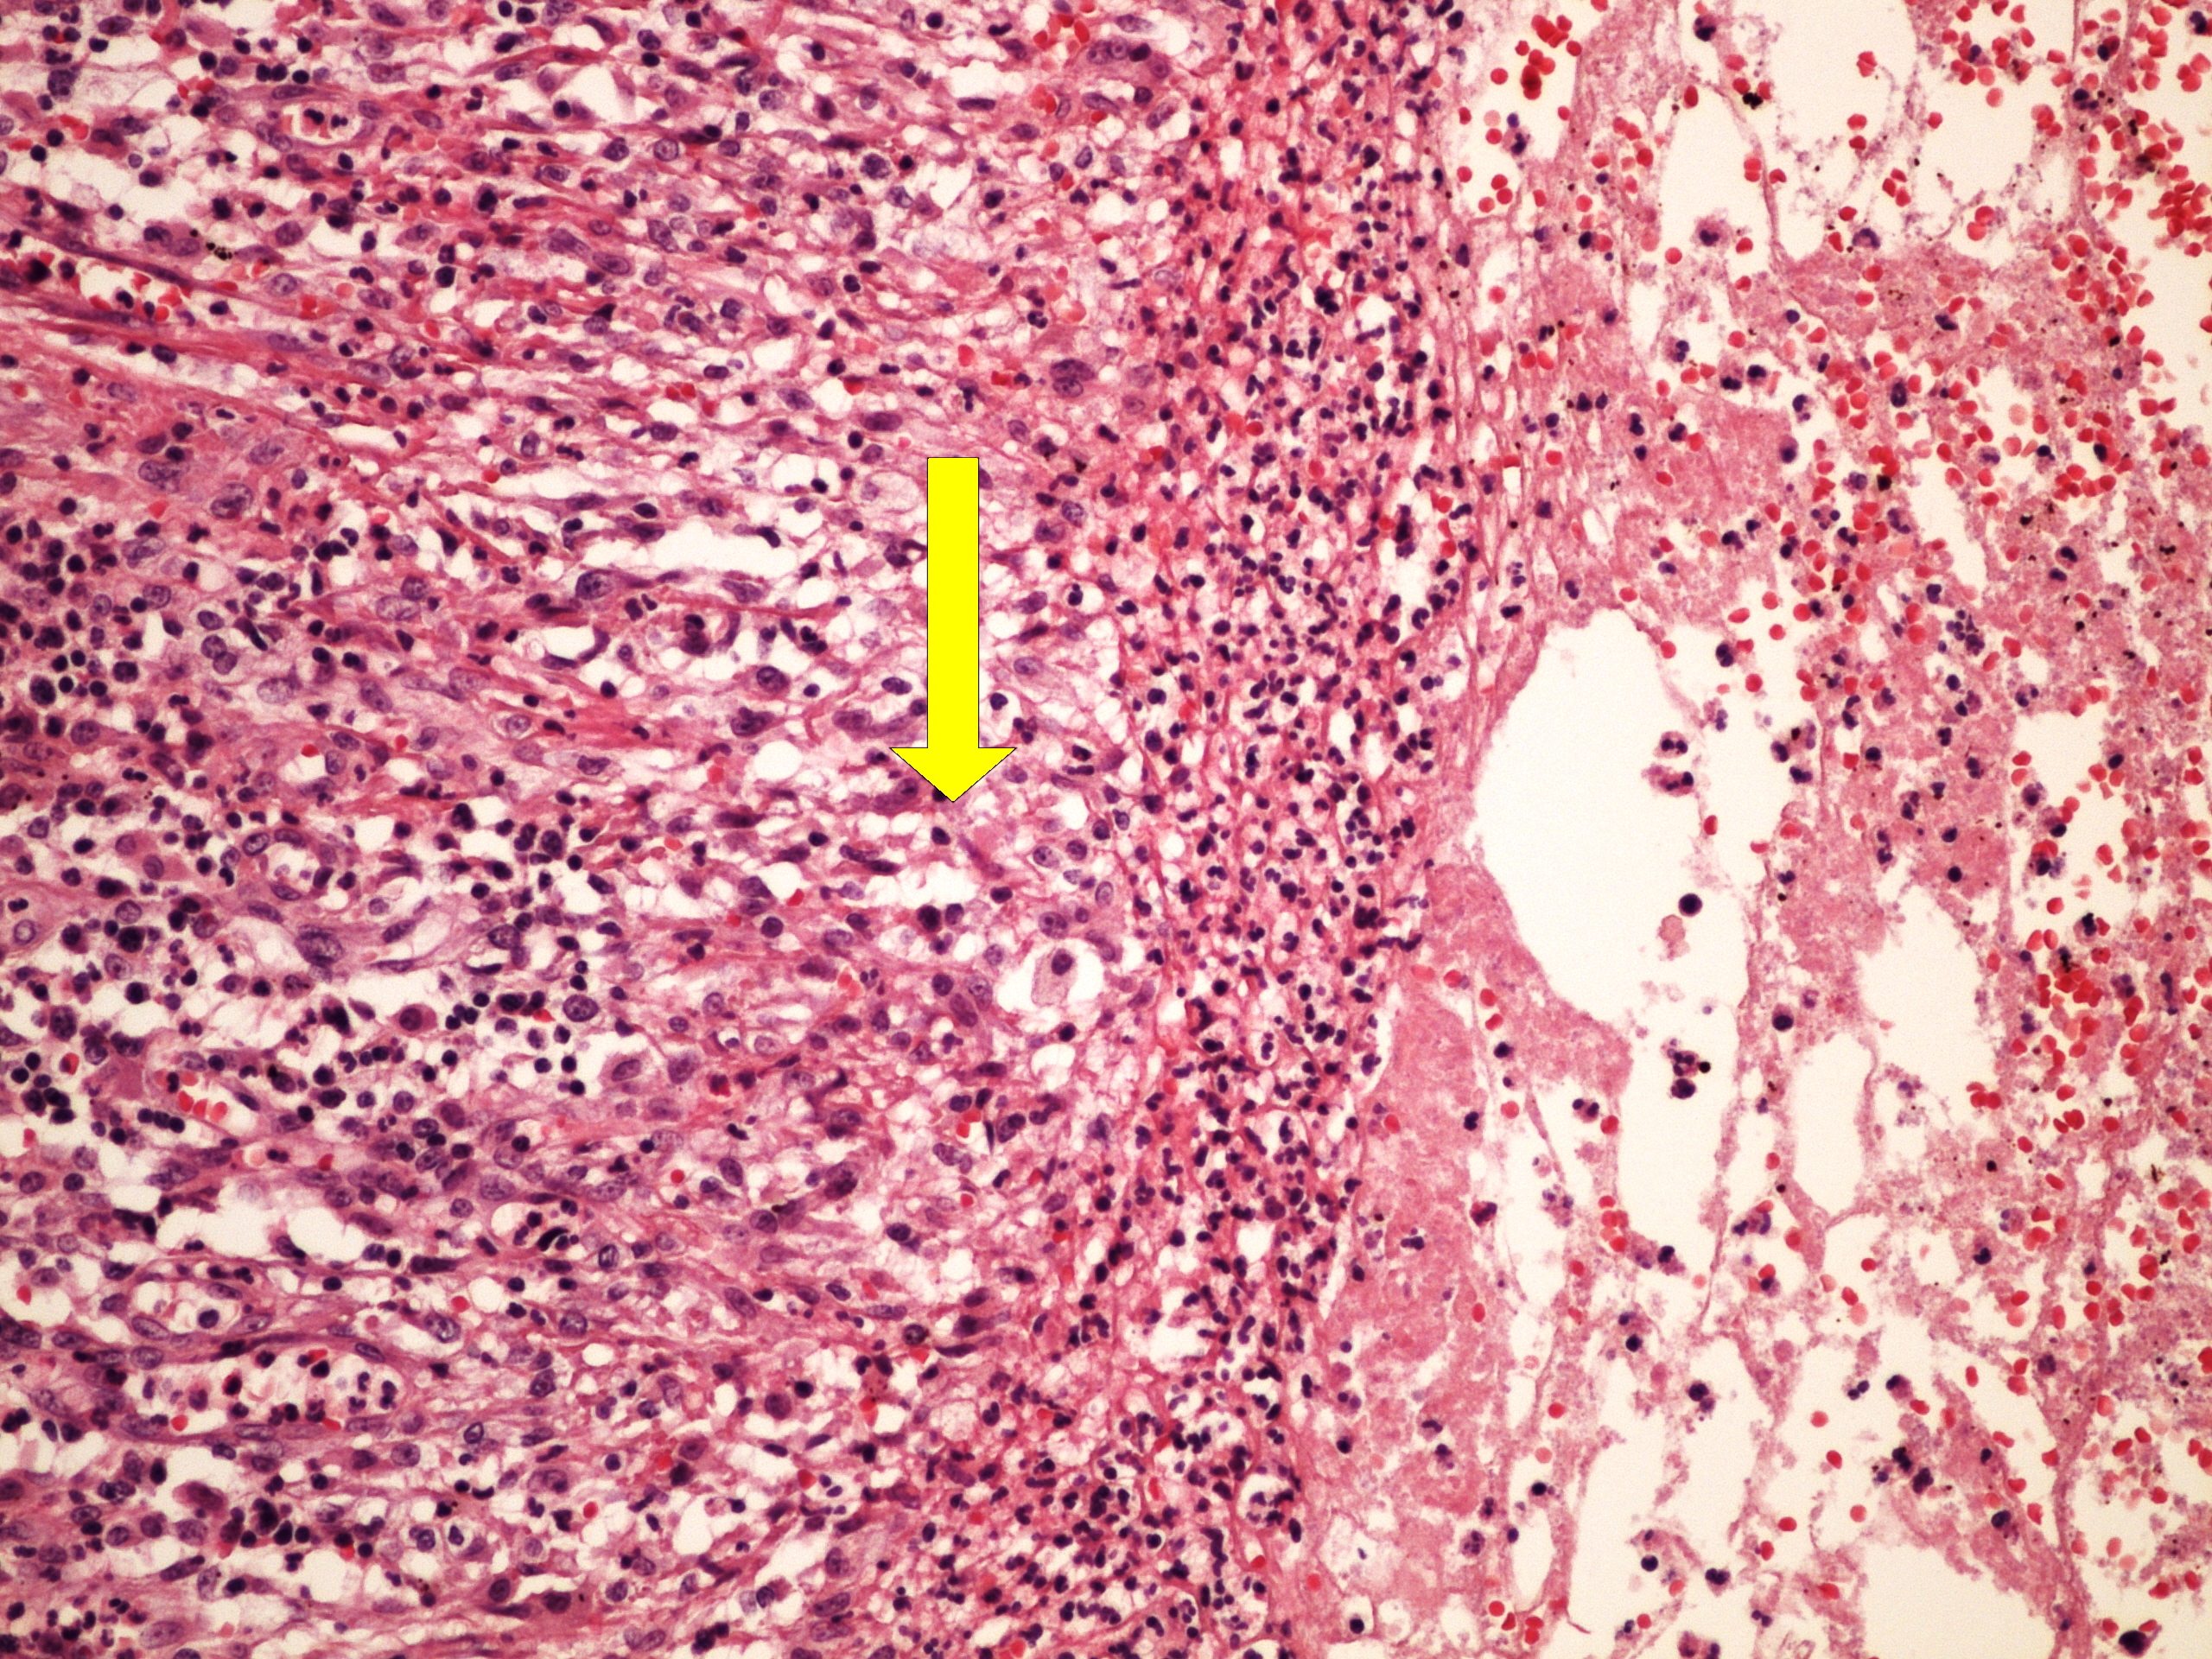

Preparát č.9 a č.10 - chronický plicní absces

Struktury

- nespecifická granulační tkáň